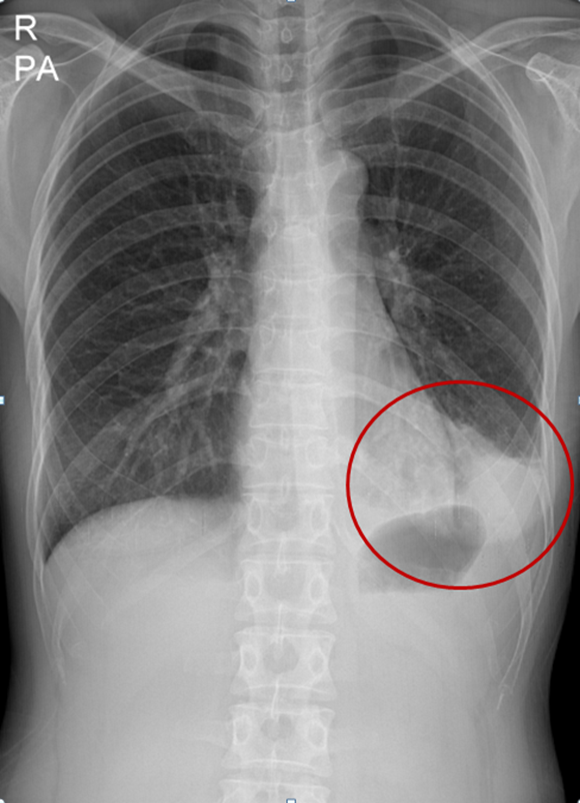

폐렴은 임상적인 증상과 X-선 검사를 통하여 진단하게 된다. 폐렴으로 진단된 후의 진료에서 가장 중요한 결정 중의 하나는 입원 여부의 결정이다. 환자의 중증도나 사망 위험도에 따라 적절하게 외래 치료 혹은 입원 치료를 결정하여야 하는데 노년층에서는 여러 동반 질환이 있는 경우가 많아 임상적인 안정상태에 도달하는 기간이 길어지므로 젊은 사람에 비해서 긴 회복기간이 필요하게 된다. 따라서 여러 동반 질환이 있는 노년층에서 입원치료 후 퇴원 시점을 결정할 때에는 조기 재활 치료를 포함한 추가적인 조치가 필요한지를 평가해야 한다.

| ▲폐렴환자의X-ray 사진.(제공=분당제생병원) |